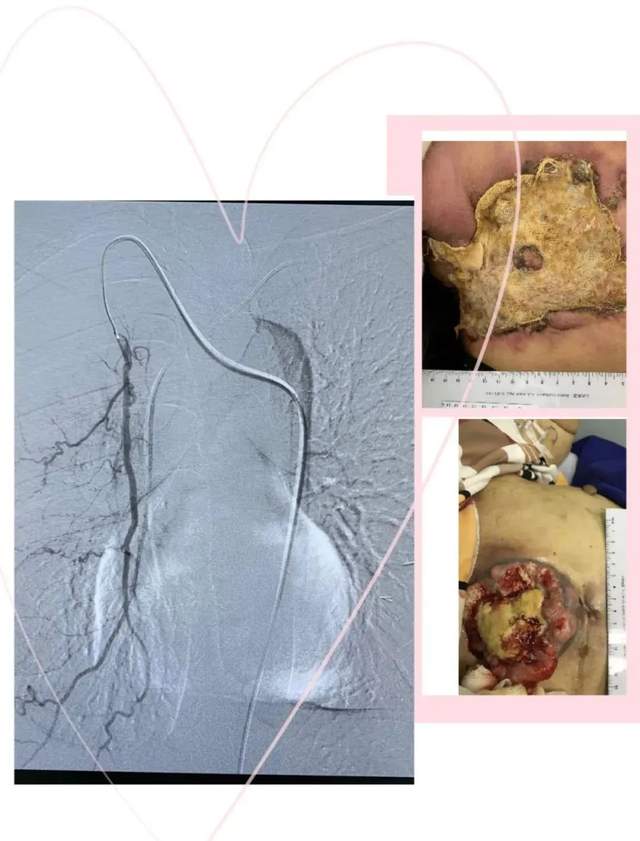

原发性肝癌血管介入

直肠癌出血栓塞

乳腺癌破溃出血

血管畸形、脾动脉破裂、肠道出血等栓塞